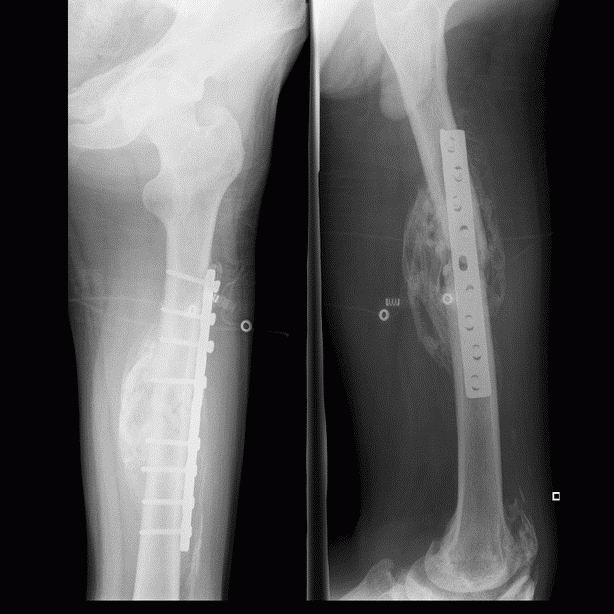

男,三十岁,多处外伤性骨折术后两月余。

骨化性肌炎:原因不明,多于外伤有关。好发于青年男性,多位于受伤部位的四肢深部组织如股四头肌、股内收肌、上臂肌及肘部肌群内,但不局限于肌肉。

临床上多有外伤史,及全身疾患如截瘫、昏迷等。早期局部肿胀、疼痛,可扪及包块,邻近关节活动受限。病理:早期为局部软组织水肿、变性、坏死、肌纤维断裂及原始间叶细胞增生形成肿块,之后肿块变硬,最外层形成成熟的纤维组织和骨组织,肿块不侵犯骨组织,但可与骨皮质相连。

影像表现为初期患处局限性肿胀,肌间隙模糊,密度增高,之后出现絮状钙化影及毛糙不整的网状致密影,邻近骨质可有骨膜反应;中期肿块内出现条状或层状钙化影,边缘部位出现致密骨。后期肿块缩小,与邻骨间以透亮带相隔或紧密相连,肿块内出现高密度钙化及骨结构形成,骨化影大部分沿肌束走行,是其重要鉴别点。需与下列疾病鉴别,1.骨外软组织骨肉瘤 2.骨外软骨肉瘤  3.皮质旁骨肉瘤 4.骨间膜钙化 5.进行性骨化性肌炎及软组织的其他钙化性疾病。

骨旁软组织内见广泛斑片条状密度增高影,考虑外伤性骨化性肌炎。